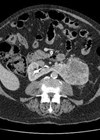

Case 1 Figure 1. A 26-year-old female presents to A&E with loin pain. What do the CT images in Figures 1 (left, centre and right) show? What is the prevalence of the congenital anomaly in the general population, and is...